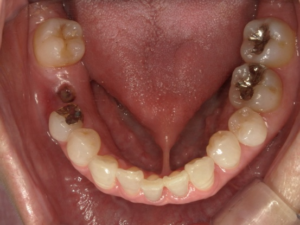

(治療前)

右下6番が欠損してることにより、噛み合わせの一部を失っていた状態です。

隣接歯があるため、ブリッジや義歯を補綴物として選択もできますが、隣接歯に負荷がかかってしまうため、予後を考えてインプラントを選択しました。